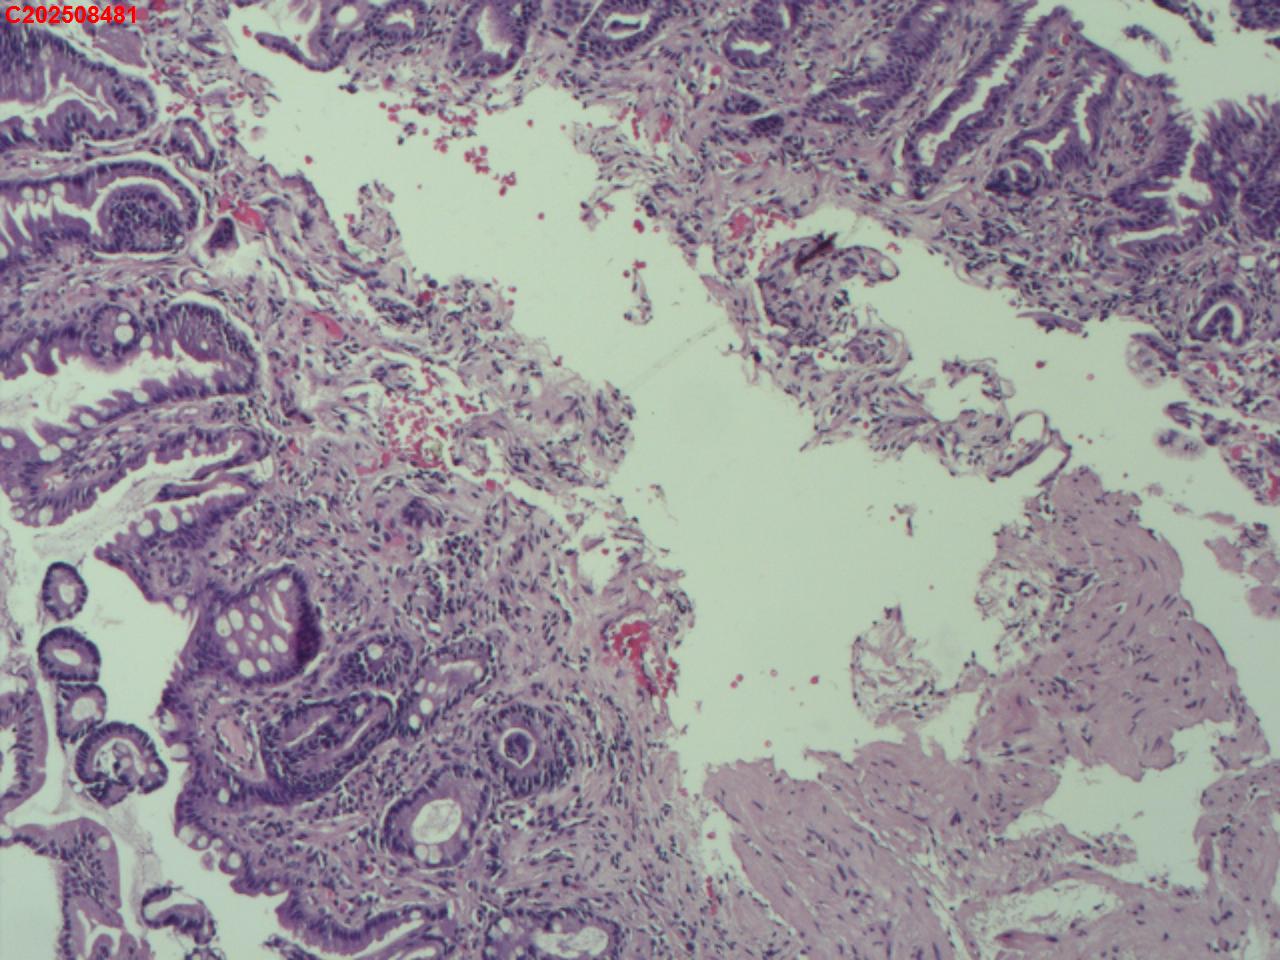

胃窦粘膜

性别

男

年龄

66岁

临床诊断

门脉高压性胃病伴糜烂

一般病史

肝硬化

标本名称

大体所见

粘膜多发片状充血、糜烂。

图1

慢性萎缩性炎,伴肠化,